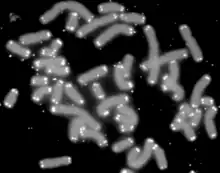

Telomere shortening

Telomeres are regions of repetitive nucleotide sequences associated with specialized proteins at the ends of linear chromosomes. They protect the terminal regions of chromosomal DNA from progressive degradation and ensure the integrity of linear chromosomes by preventing DNA repair systems from mistaking the ends of the DNA strand for a double strand break.

Telomere shortening is associated with aging, mortality and aging-related diseases. Normal aging is associated with telomere shortening in both humans and mice, and studies on genetically modified animal models suggest causal links between telomere erosion and aging.[10] Leonard Hayflick demonstrated that a normal human fetal cell population will divide between 40 and 60 times in cell culture before entering a senescence phase. Each time a cell undergoes mitosis, the telomeres on the ends of each chromosome shorten slightly. Cell division will cease once telomeres shorten to a critical length.[11] This is useful when uncontrolled cell proliferation (like in cancer) needs to be stopped, but detrimental when normally functioning cells are unable to divide when necessary.

An enzyme called telomerase elongates telomeres in gametes and stem cells.[12] Telomerase deficiency in humans has been linked to several aging-related diseases related to loss of regenerative capacity of tissues.[13] It has also been shown that premature aging in telomerase-deficient mice is reverted when telomerase is reactivated.[14] The shelterin protein complex regulates telomerase activity in addition to protecting telomeres from DNA repair in eukaryotes.